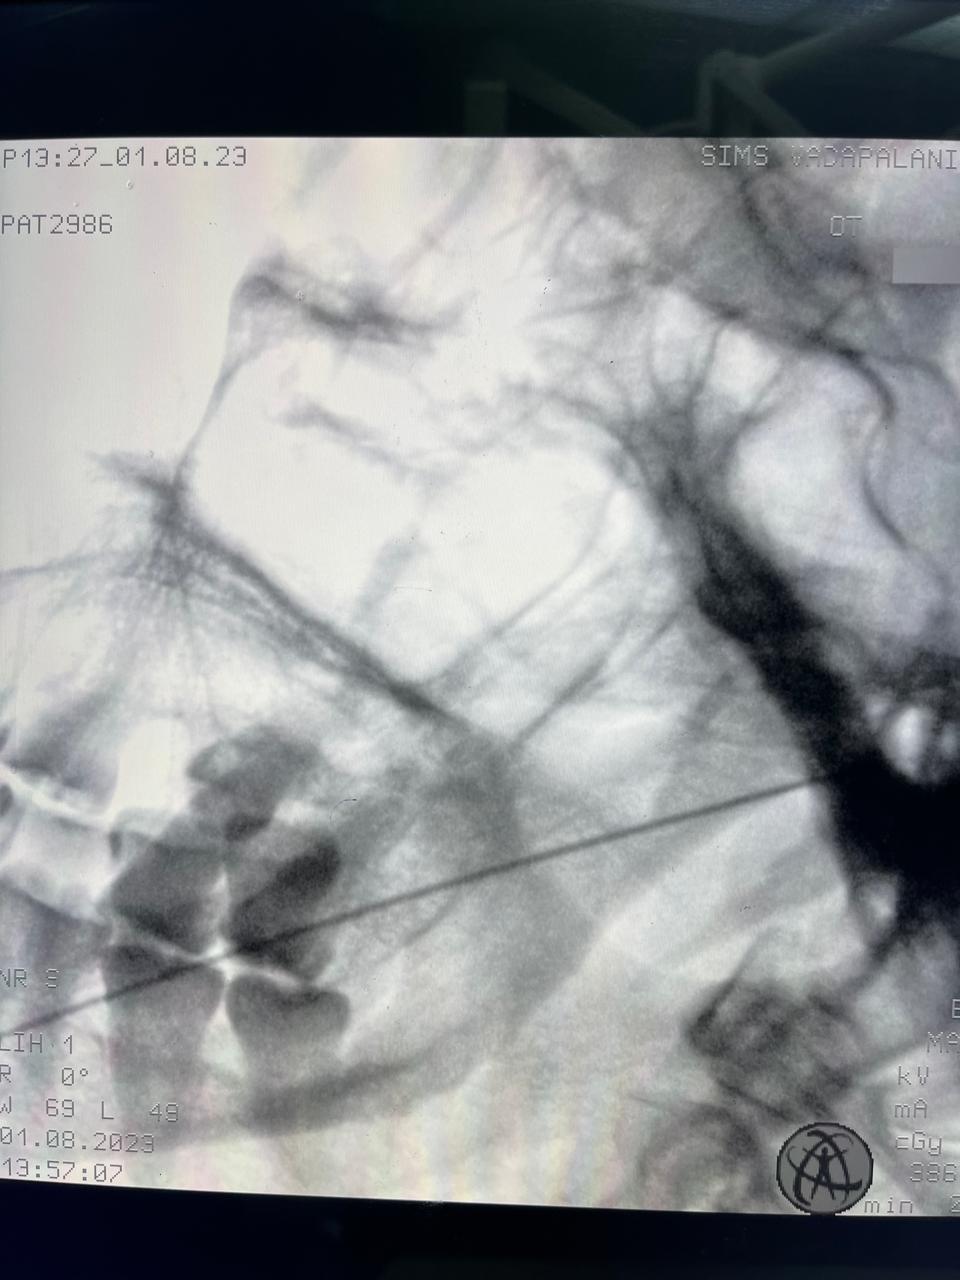

At RK Pain Management Clinic, we are dedicated to providing comprehensive, compassionate care to individuals suffering from chronic pain.